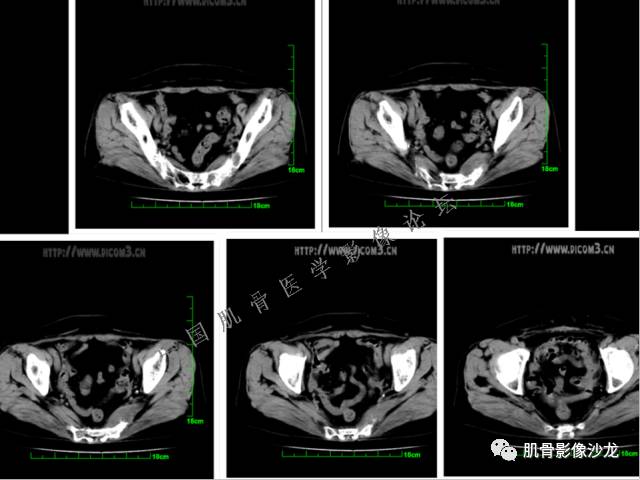

1、软骨肉瘤可以有膨胀性骨质破坏(病例3,4),可以有溶骨性骨质破坏(病例2),局部皮质因为破坏变薄,中断 ;

2、软骨基质T2WI高信号,软骨小叶分叶状,也就会出现高老师提到的骨内膜扇贝形压迹。一般认为骨内膜扇贝形压迹超过骨皮质厚度的2/3是软骨肉瘤在长管状骨的特征性表现。如上图。3、软组织肿块或肿胀;

4、 钙化,环形,弓形,边缘模糊 ;

5、增强后进行性延迟,不均匀分割状强化, 会强化的纤维间隔,软骨小叶不会强化,关于老师们说到的钙化,软骨肉瘤不一定会有钙化 。

2、软骨肉瘤的发病部位排名:最好发部位为髂骨,其次股骨、肱骨和脊柱。